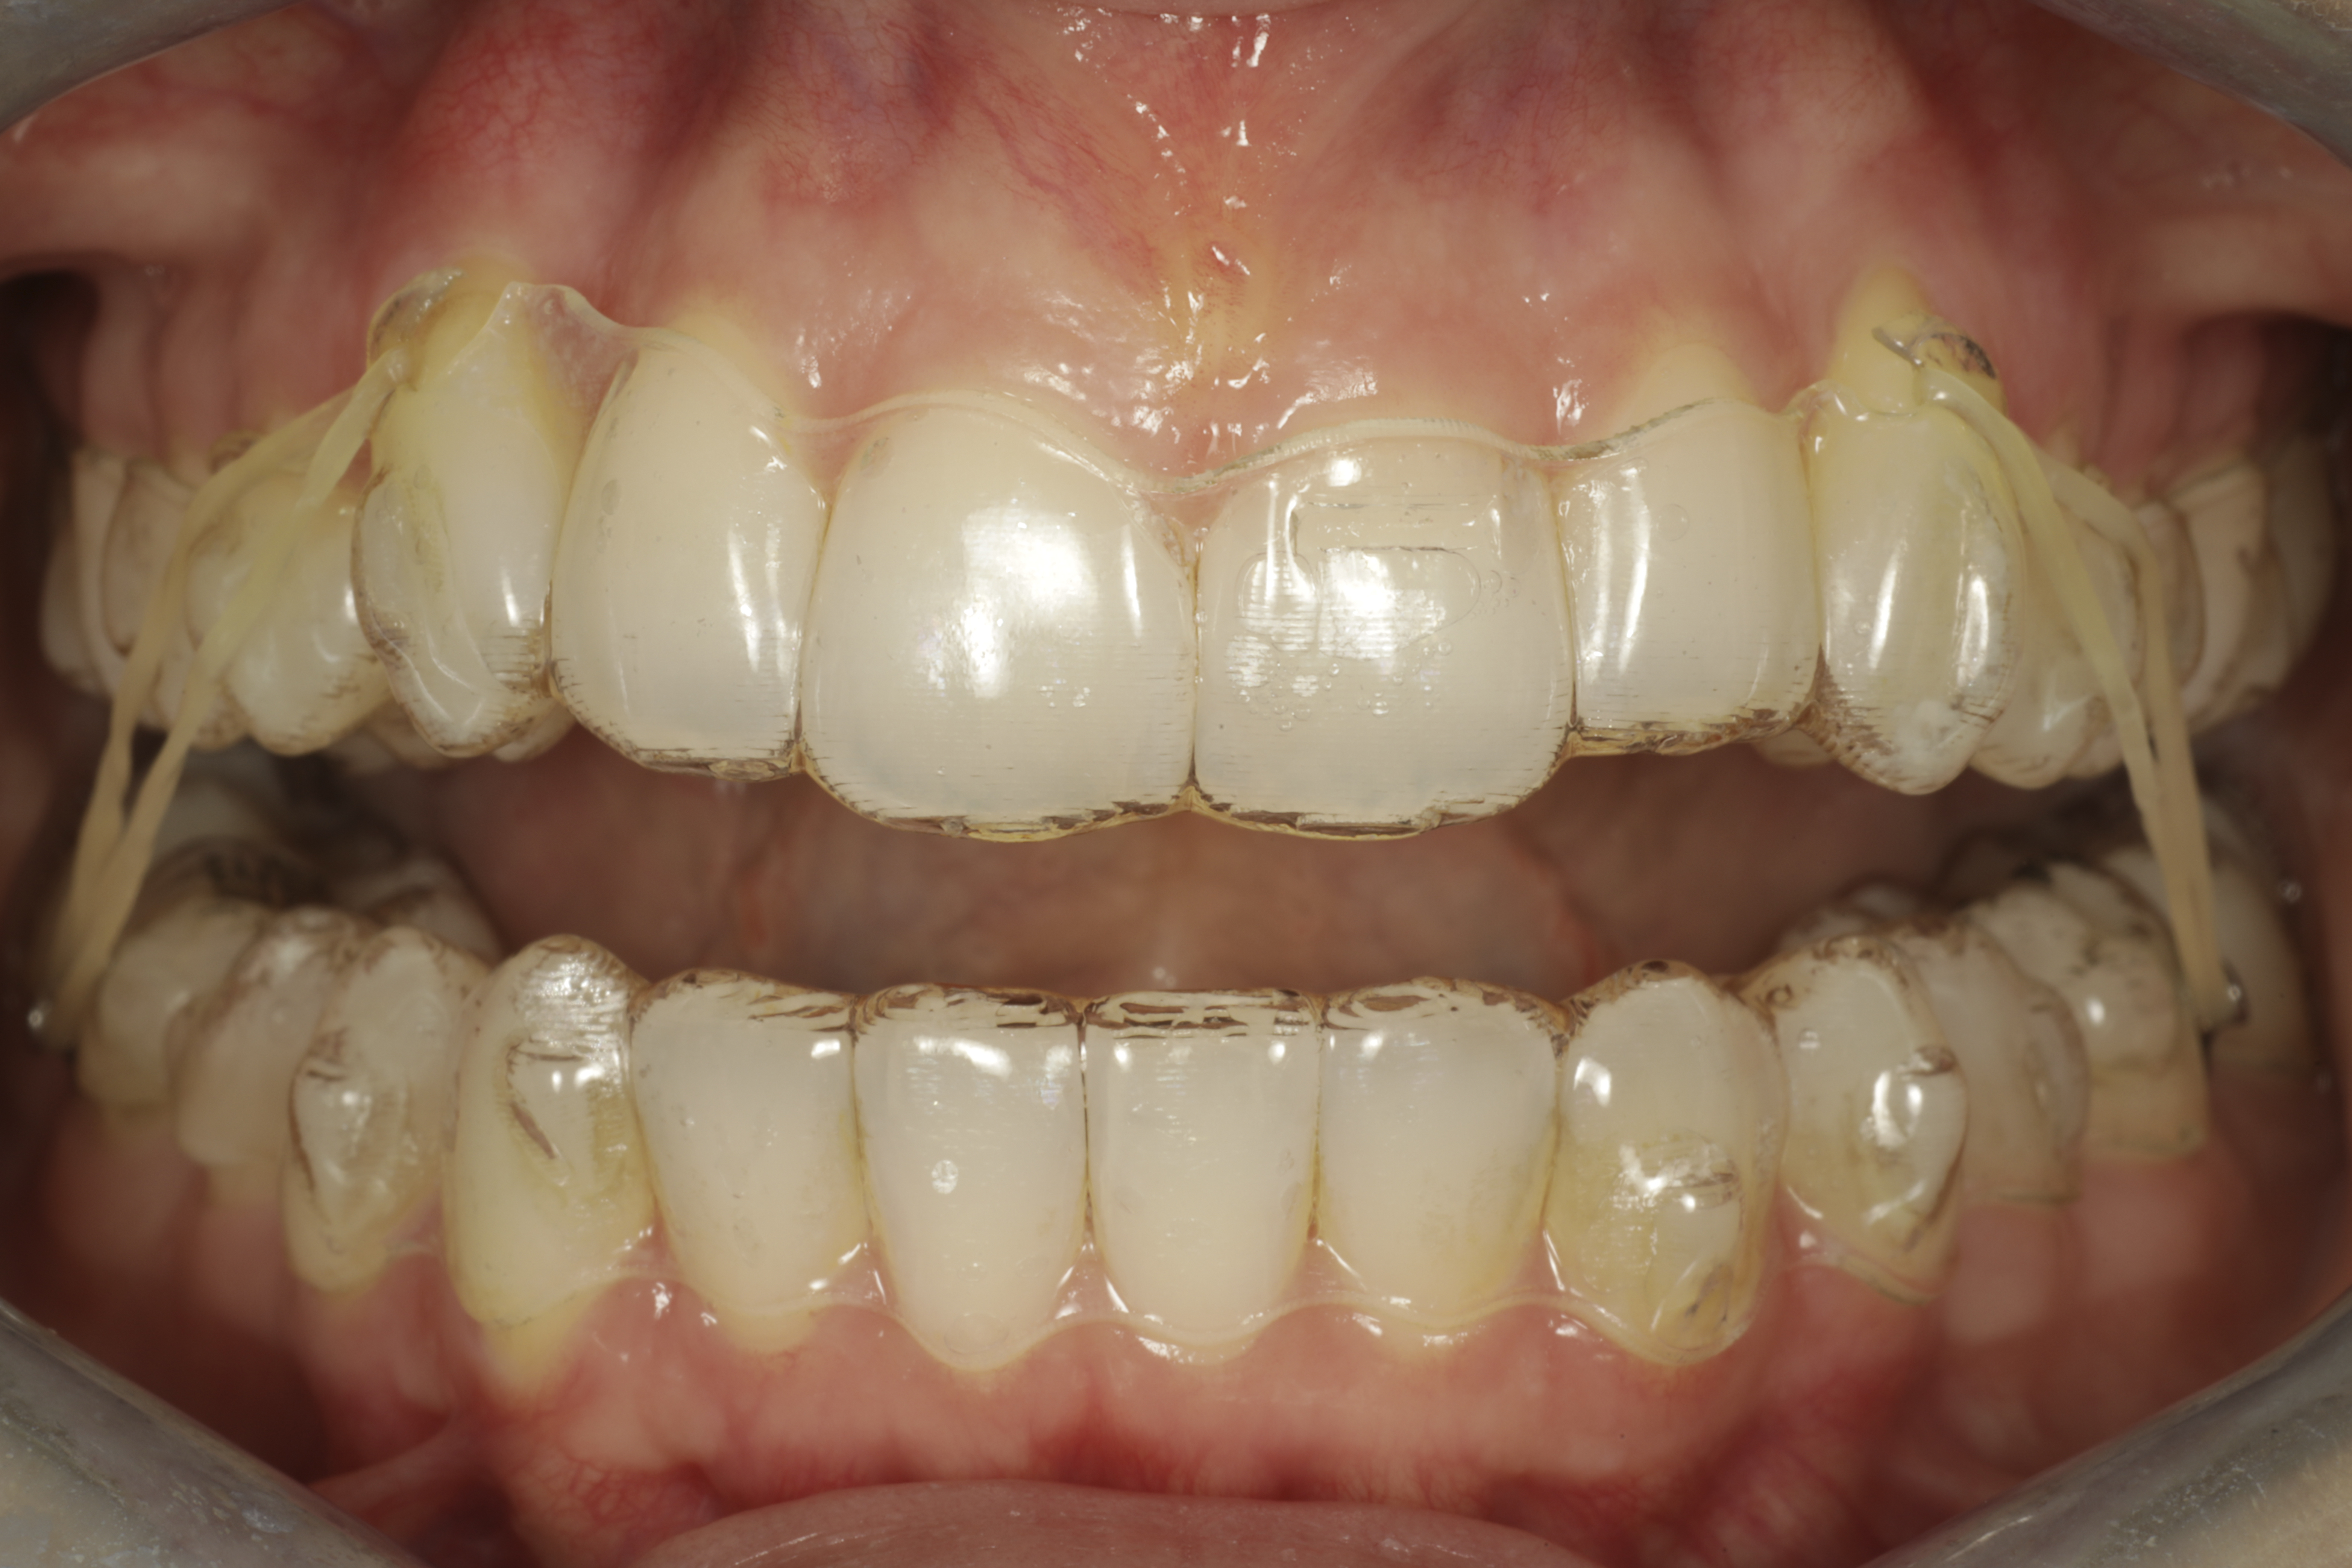

Eli se mikä hoidossa kiinnostaa eniten. Kuinka huomaamatonta se oikeasti on? Pelkillä kalvoilla ei saa kaikkia liikkeitä toteutumaan. Hampaisiin tarvitaan tiettyjä liikkeitä tehostamaan hampaan värisestä paikkausmuovista tehtyjä tarttumakohtia kalvoille eli kiinnikkeitä. Esimerkiksi pyöreän mallisten hampaiden kiertämiset eivät onnistu pelkillä kalvoilla ilman tarttumiskohtaa hampaissa. Kiinnikkeet kiinnitetään hampaisiin hoidon alkuvaiheessa ja ne ovat paikoillaan hoidon ajan. Ne poistetaan hampaiden pintoihin jälkiä jättämättä kun hampaat ovat oiottu halutuille paikoilleen.

Alkutilanne

Kiinnikkeet paikoillaan

Lopputulos